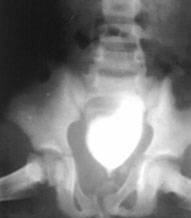

2.尿道或膀胱损伤。对骨盆骨折的病人应经常考虑下尿路损伤的可能性,尿道损伤远较膀胱损伤为多见。患者可出现排尿困难、尿道口溢血现象。双侧耻骨支骨折及耻骨联合分离时,尿道膜部损伤的发生率较高。

2. 尿道或膀胱损伤。对骨盆骨折的病人应经常考虑下尿路损伤的可能性,尿道损伤远较膀胱损伤为多见。患者可出现排尿困难、尿道口溢血现象。双侧耻骨支骨折及耻骨联合分离时,尿道膜部损伤的发生率较高。